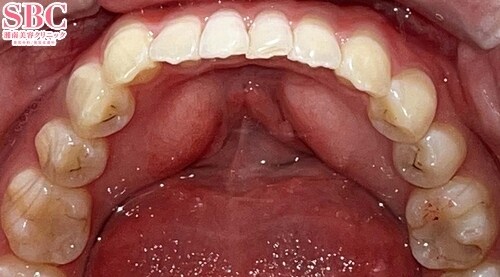

No.350922【美容歯科】【本当にかわいくなりたい人は竹本佳子院長】インビザラインモデレート(両顎)/20代女性/ガタつき・捻じれ

施術前

下の歯の写真ですが、特に前歯4本のガタつきが気になりますね

施術後9ヶ月後

ガタつきも無くなりキレイなアーチ状の歯並びになりました♪